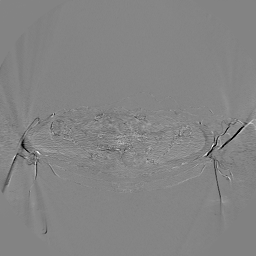

The results for simulated noisy data are shown in Fig. 2. The first and third rows display two representative slices from the test set, and the second and fourth rows present the corresponding error maps. The traditional WCE method suppresses cupping artifacts and recovers some missing anatomical structures but still shows noticeable deviations from the ground truth. Predictions from the four diffusion-based models demonstrate a markedly improved ability to restore anatomical structures. Among them, cDDPM fails to fully reconstruct the patient bed and retains residual noise in its outputs. This noise is attributable to an incomplete reverse denoising process rather than residual Poisson noise, as evidenced in our noise-free experiments (Fig. 5 in the Appendix). PatchDiffusion, diffusionGAN, and I2SB achieve similar visual quality, with I2SB producing the cleanest and most consistent reconstructions.

Quantitative results in Tab. V further confirm I2SB’s superiority over conventional deep learning methods such as FBPConvNet and Pix2pixGAN across RMSE, PSNR, and SSIM. Compared to other diffusion models—including cDDPM, PatchDiffusion, and cLDM—I2SB delivers higher image quality, while diffusionGAN achieves comparable quantitative performance. However, I2SB demonstrates a significant advantage in inference efficiency, as summarized in Tab. IV.